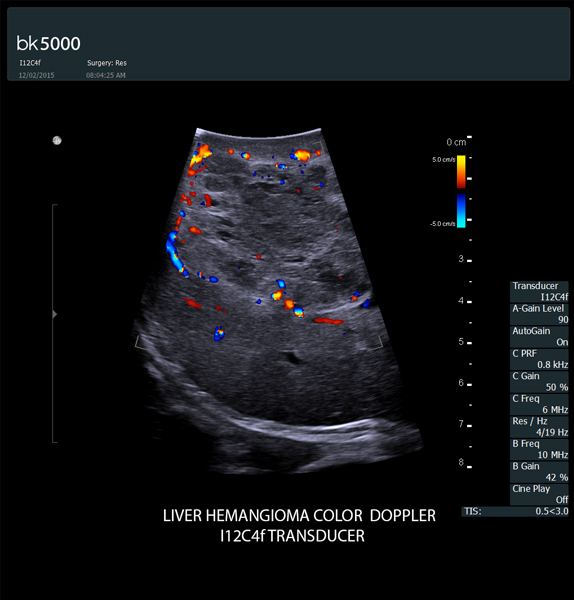

Ultrasound can advance intraoperative surgical procedures by helping you navigate and identify lesions and anatomical structures in real-time. This is particularly important as the data obtained from a preoperative CT or MRI scan can be outdated at the time of surgery.

The bk5000 surgical system provides the highest quality images that allow you to clearly see the margins of a lesion and to determine the best course of action. Using advanced graphics processing technology, this powerful system provides immediate, auto-optimized images that allow you to see the information you need, faster.